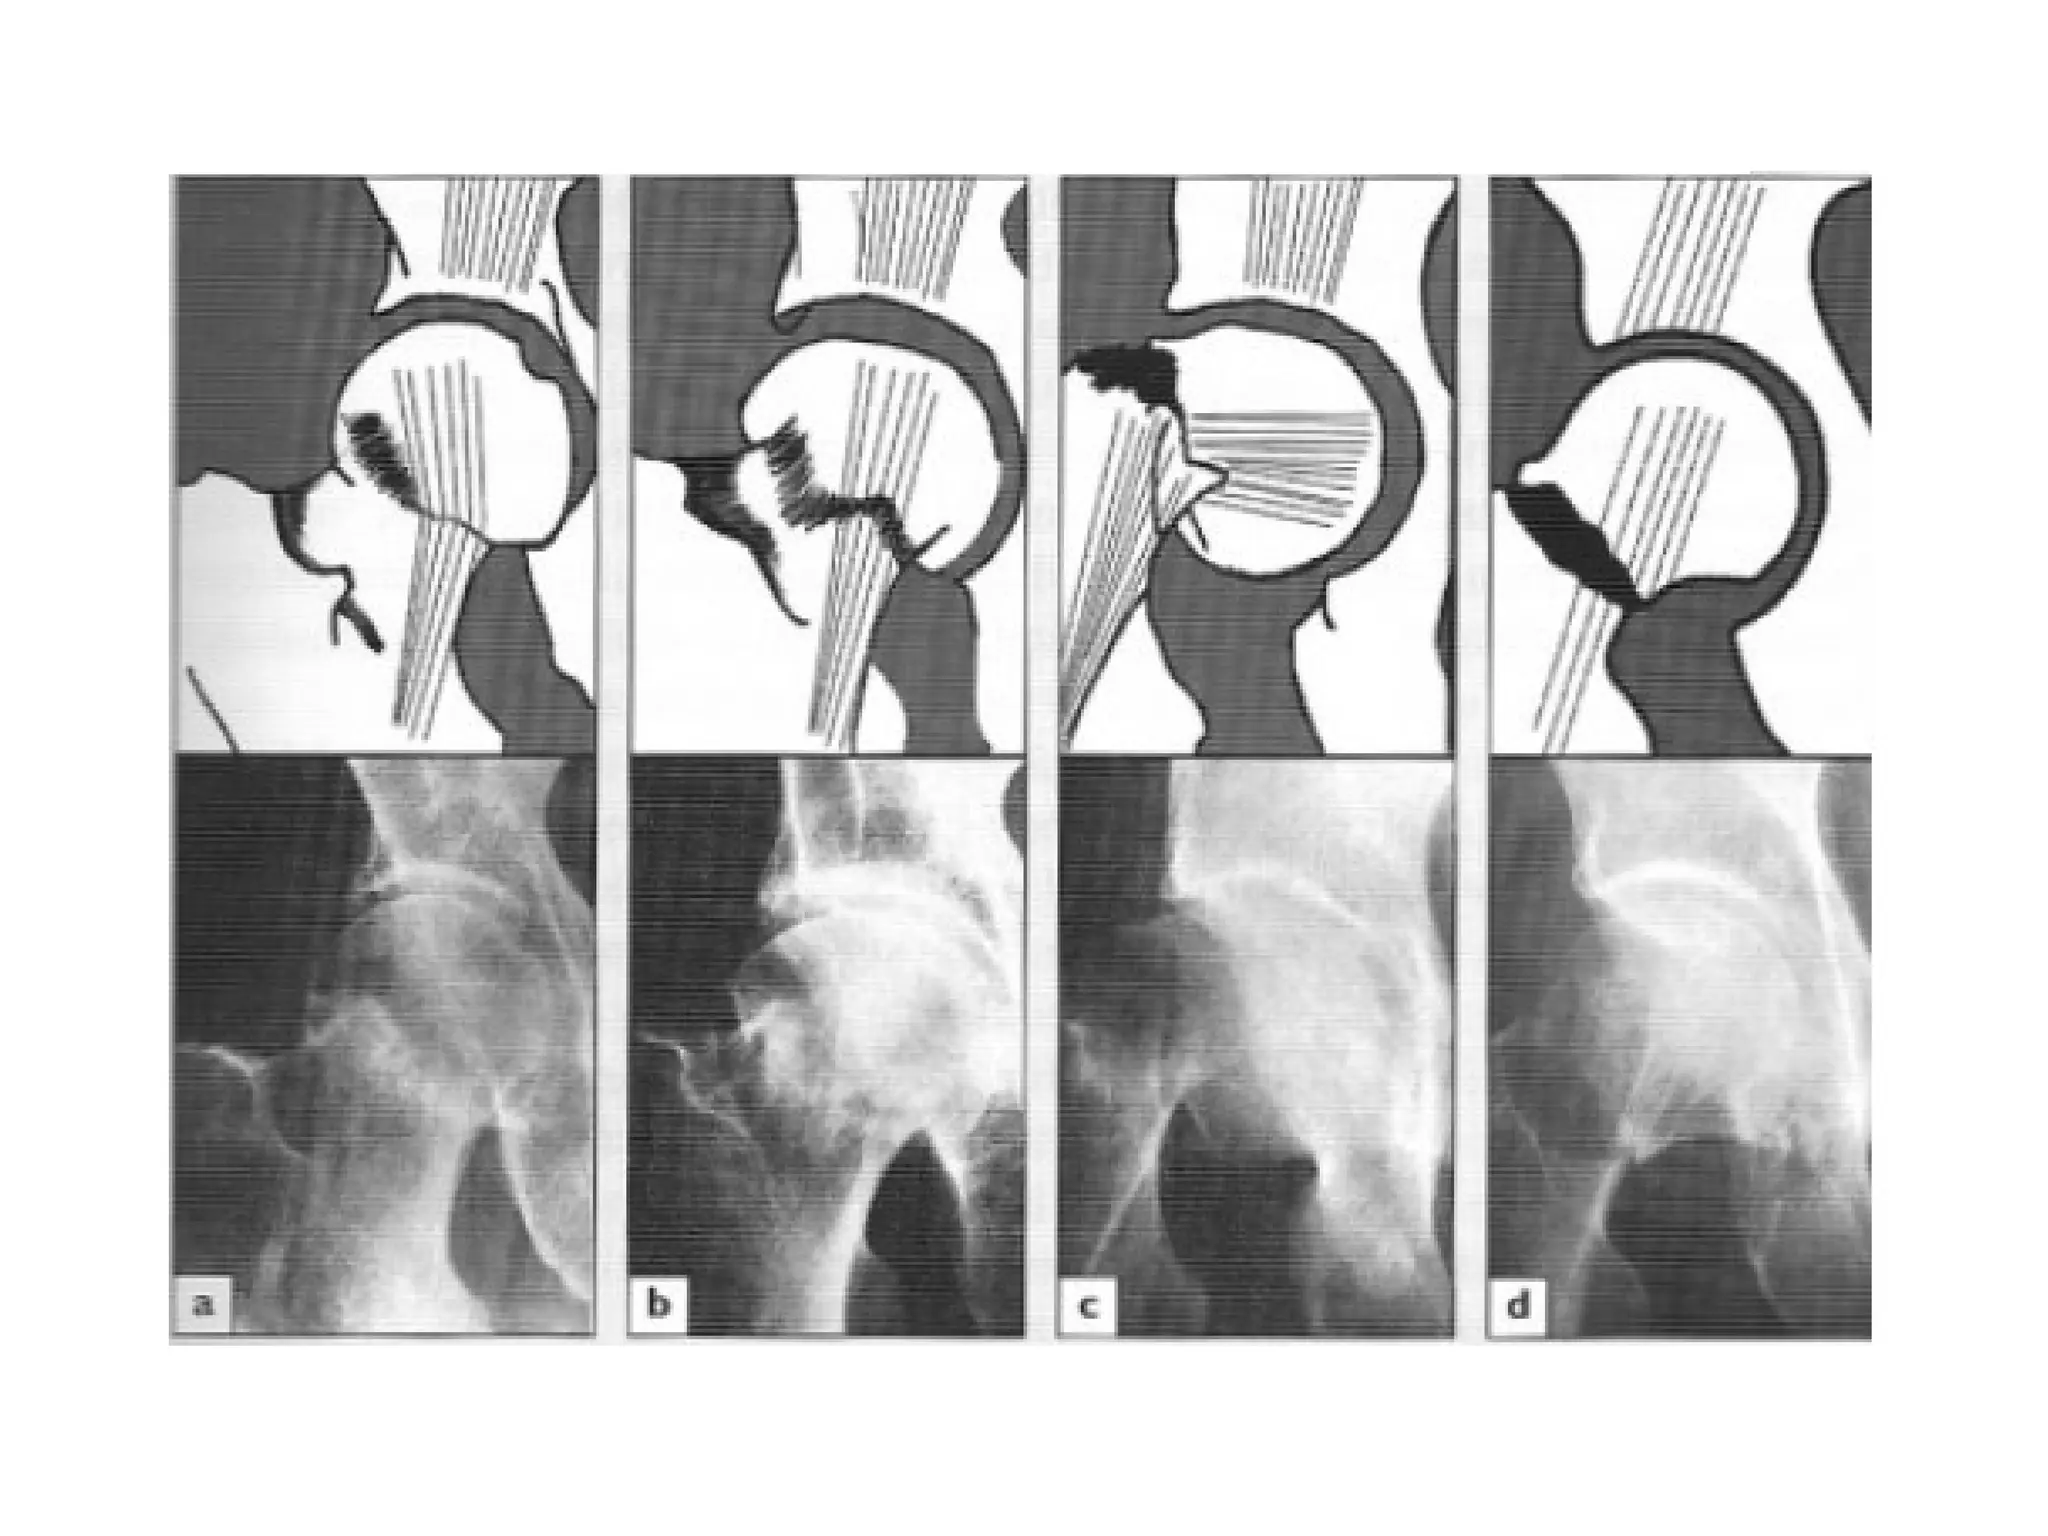

• Garden’s Classification:

• Based on the amount of displacement in the Pre-reduction

X-ray (Radiological)

• Stage І : Incomplete undisplaced Fracture (impacted or

abducted)

• Stage II : Complete undisplaced Fracture

• Stage ІІІ : Complete with moderate displacement

• Stage IV : Complete with severe Displacement

• Any downstage may progress to upstage if left untreated

• X-ray:

• Is there a fracture, and is it displaced?

• Usually Break is obvious but impacted one can be missed

• Displacement (abnormal shape of bone outline, mismatch

of the trabecular lines)